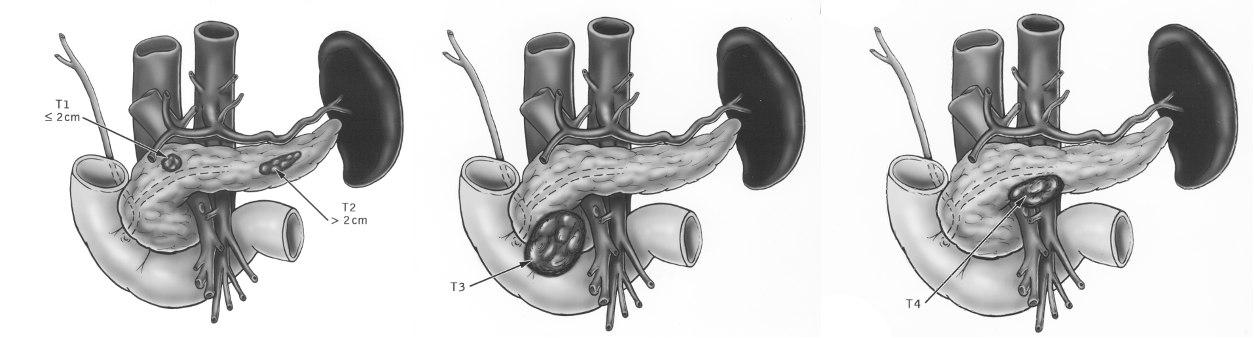

Tumor Staging according to the TNM System

T1 = <2cm

T2 = 2-5 cm

T3 = >5 cm

T4 = Invasion of adjacent tissue

n1 peripancreatic ln n2 far from origin